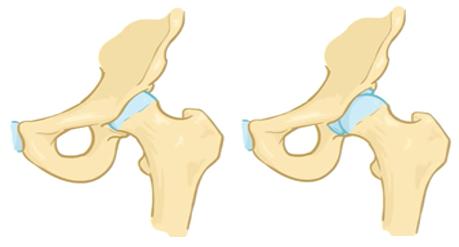

我们正常的髋关节是由髋臼和股骨头构成的,髋臼相当于一个“碗”,股骨头相当于一个“球”,日常活动中,整个关节被关节囊包裹在一个密闭的空间内,髋臼这个“碗”将股骨头这个“球”包裹住,使它不会跑出去,而“球”在“碗”的包裹下,可以做各个方向的旋转。

而髋关节发育不良的患者,髋臼这个“碗”发育得没那么好,表现为这个“碗”不够深,“碗”变浅了,那么股骨头这个“球”就有向“碗”外面跑的趋势。

正常髋关节与髋关节发育不良